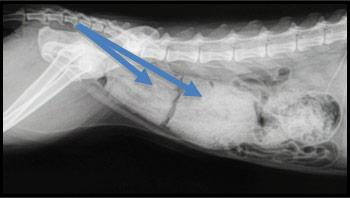

- Fracture du bassin : Un déplacement des fragments osseux peut réduire l’espace de passage du côlon, entraînant une obstruction.

- Présence d’une masse abdominale : Une tumeur ou un autre type de masse peut comprimer le côlon et gêner l’évacuation des selles.